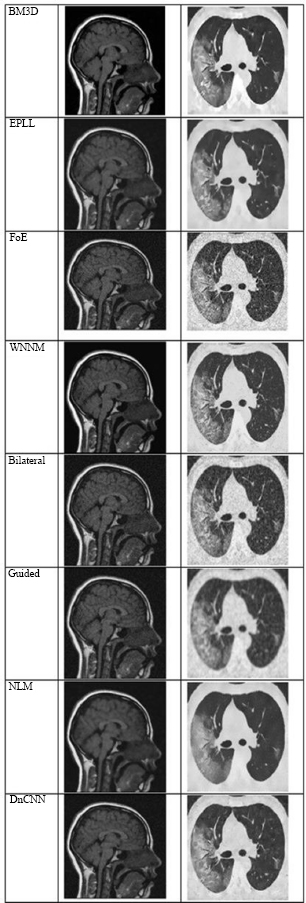

Fig. (4) shows the results at a noise variance of 0.01, where it has been observed that all algorithms produce clear images, except for the Guided algorithm.

Fig. (5) shows the results at a noise variance of 0.05, where it has been observed that the BM3D, EPLL, and WNNM algorithms produce clearer images compared to other algorithms. NLM and DnCNN also perform well, but not as well as the above-mentioned three algorithms.

Fig. (6) shows the results at a noise variance of 0.09, where it is observed that the BM3D, EPLL, and WNNM algorithms produce clearer images compared to other algorithms. Another algorithm, DnCNN, also performs well, but not so well as the above-mentioned three algorithms.

Fig. (7) shows the results at a noise variance of 0.5, where it has been observed that all the algorithms produce blurred images, except for the BM3D algorithm. However, the results of the BM3D algorithm are not so satisfactory. As a result, it has been observed that at a noise variance of 0.5, none of the algorithms performed well.

It has been observed that, except for the Guided Filter, which was unable to preserve edge details successfully, most algorithms presented visually clear and good results at low noise levels (variance = 0.01). Techniques such as BM3D, EPLL, and WNNM consistently produced better quality and detail preservation than others in terms of their visual quality and detail preservation at medium noise levels (variance = 0.05 and 0.09). Although their performances were commendable, those of NLM and DnCNN were slightly less accurate and reliable.

All the algorithms performed poorly at the high-noise level (variance = 0.5), producing significantly distorted and degraded images. At this level of noise, even BM3D, which had demonstrated relative robustness, could not produce outputs appropriate for diagnosis. This result highlights the limitations of current denoising methods in high-noise or low-SNR conditions that are common in low-dose or accelerated medical imaging scenarios.

To demonstrate the clinical importance of denoising, a comparison is made between noisy and denoised sagittal T1-weighted MRI images. The noisy image may be difficult to diagnose due to its grainy texture and low contrast of tissue structures, as significant structures, such as the brain stem, thalamus, and corpus callosum, are obscured. These make a lot more sense post-denosing, enabling the assessment of subcortical integrity, the inspection of ventricular pathways, and the secure differentiation of gray and white matter. These improvements are not limited to visual interpretation; their direct application to early detection and treatment planning of diseases such as hydrocephalus, multiple sclerosis, and brain tumors firmly places them within the medical field.

To highlight the clinical significance of denoising, a comparison is performed of the visual and anatomical enhancements visible in high-resolution chest CT images. In the initial HRCT model with noise, the clarity of the bronchial walls, pulmonary vessels, and interstitial markings was greatly affected by high-frequency noise, which is important for the identification of certain lung diseases, such as fibrosis, bronchiectasis, or pulmonary infections. Following the denoising process, restored soft tissue contrast and improved visualization of segmental bronchi, vascular branches, and pleural boundaries were observed in the resulting image. Such improvements have a direct impact on the confidence of radiologists, the predictability of lesions, and the probable reduction of false diagnoses. Accordingly, technical validation using PSNR and SSIM was achieved, while the clinical advantage of the denoising procedure was demonstrated by the preservation of diagnostically important structures crucial for accurate thoracic interpretation.